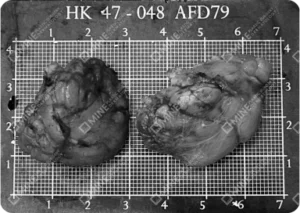

Check Removed Salivary Glands with Your Own Eyes

At MINE Plastic Surgery,

based on extensive experience in salivary gland removal procedures,

we show you the actual glands and fat tissues removed during surgery.

Large saliva gland tissues displayed post salivary gland removal surgery.

Two gland samples shown side by side that were removed after salivary gland removal procedure.

*Actual saliva gland that was removed from surgery patients at MINE.